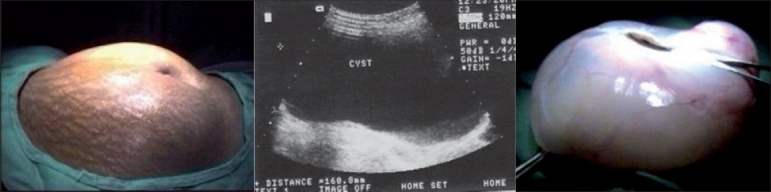

Materials and methods: Fifteen patients from March 2004 to February 2007, with large ovarian cysts, with diameter >10 cm, were managed laparoscopically. The masses were cystic and were not associated with ascites or enlarged lymph nodes on ultrasound. Serum CA-125 levels were within the normal range (35 U/ml). Preoperative evaluation included history, clinical examination, sonographic images and serum markers. The management of these ovarian cysts included aspiration, cystectomy or salphingo-oophorectomy, depending on the patient's age, obstetric history and desire of future fertility. In large, solid, fixed or irregular adnexal masses, suspicious of malignancy, laparotomy was done.

Results: Five patients presented with pain in the abdomen and 10 patients with abdominal distension and discomfort. The average maximum diameter of the ovarian cysts was 16.75 cm (range 10-24 cm). The mean duration of the operation was 80 min. The postoperative hospital stay was from 4 to 6 days. No intraoperative complications occurred and the hospital course of all patients was uncomplicated. In one case, laparoscopy was converted to laparotomy. One patient had minor wound infection at umbilical port site. The patients did not report any complaints during follow up and the clinical examination findings were normal in all, up to 9 months after discharge.